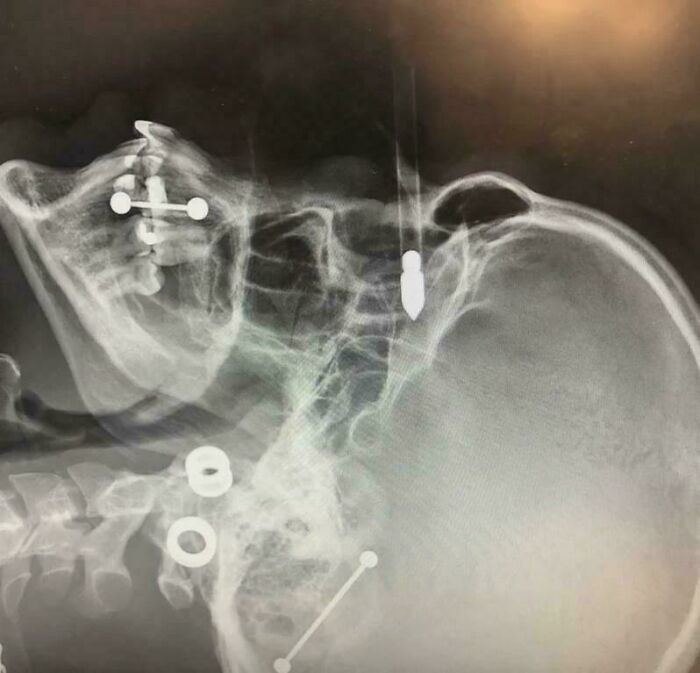

Penetrating Branch Root Injury In A Motorcycle Enduro Rider!

During an off-road motorcycle enduro race, the individual faced a difficult part of the track covered in dense plants and branches hanging overhead.